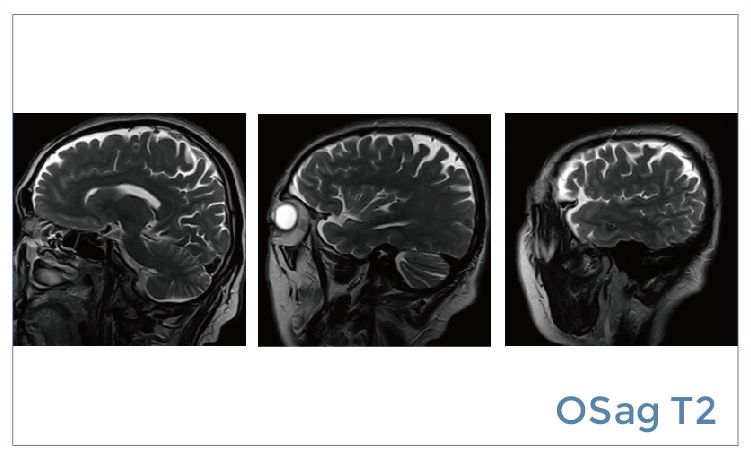

【朗润影像档案】20190531磁共振影像病例结果讨论

【朗润影像档案】磁共振影像病例分享(编号20190531)